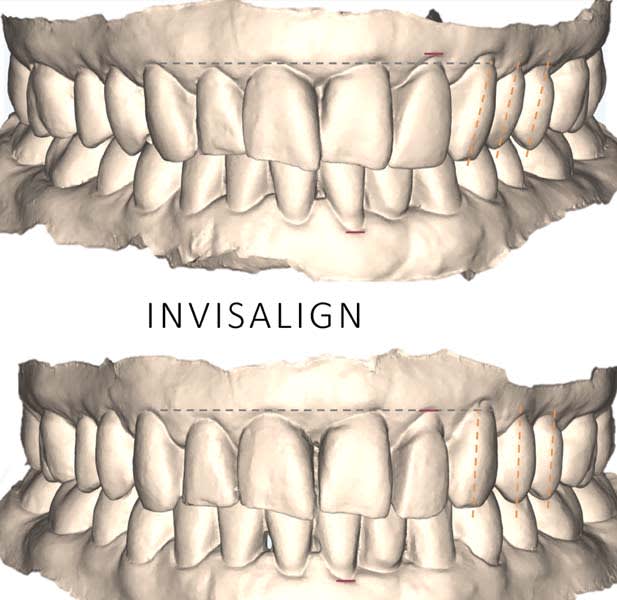

Dentofacial: The patient expressed concerns about mismatching tooth color, shape, and position. Her lip moved 10 mm from repose to Duchenne smile, placing her in the high end of normal range (6 mm to 10 mm).3 Gingival margins were uneven with supraeruption present resulting in a diagnosis of dentoalveolar extrusion with wear.4 Tooth rotations and overlaps were present as was a “black triangle,” ie, missing papilla, between teeth Nos. 9 and 10 due to the 6.8 mm distance between the crestal bone and contact point (Figure 7 and Figure 8).5 Pronounced negative buccal corridors were evident. Gingival tissue was displayed while smiling, giving the patient a high-risk dentofacial diagnosis.

The use of clear aligners (Invisalign) for 12 months achieved the following:

Gingival margin leveling: Dentoalveolar extrusion and wear were addressed by intruding the maxillary anterior teeth, gingival margins were leveled relative to CEJs, and tooth No. 10 was extruded to coronally position tissue and bone (Figure 9). The latter also reduced the black triangle and maximized the predictability of the esthetics for a future pontic site, as tooth No. 10 had a guarded prognosis.7

Clear aligners (Invisalign) were used to correct gingival margin discrepancies, reduce the black triangle between teeth Nos. 9 and 10, and optimize occlusal forces by uprighting posterior teeth. This orthodontic phase, paired with airway considerations, enabled functional and esthetic improvements without compromising tongue space. Establishing adapted centric posture via deprogramming created a stable occlusal scheme, thereby minimizing risks of further attrition or restoration failure. Lithium-disilicate crowns and resin infiltration restored function and delivered a natural, esthetic smile, with precise laboratory collaboration ensuring accurate shade and contour.